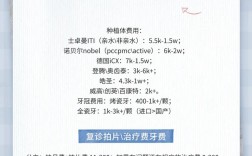

种植系统与材料:

(图片来源网络,侵删)

(图片来源网络,侵删)- 种植体品牌: 提供哪些主流国际知名品牌?(如瑞士的Straumann(士卓曼)、瑞典的Nobel Biocare(诺贝尔)、德国的Ankylos(安格斯)、美国的Zimmer(捷迈)、韩国的Osstem(奥齿泰)、Dentium(登腾)等),不同品牌在技术、设计、临床数据、长期成功率、价格上有所差异,了解医生推荐的品牌及其理由。

- 牙冠材料: 提供哪些牙冠选择?(如全瓷冠、烤瓷冠等),全瓷冠美观、生物相容性好,是目前的主流选择。

- 材料来源: 是否使用正规渠道来源的、有明确标识和保质期的产品?要求查看产品包装和说明书。